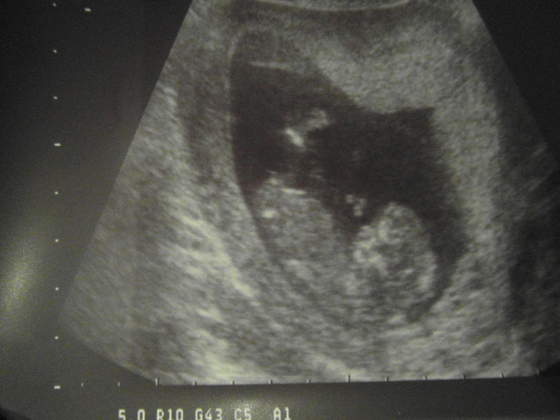

oglądam te wszystkie linki o nube i nasz wygląda tak SAM_1890.jpg fota z 12t2d co sądzicie o naszym nub? :-)

LOVE ja obstawiam na chłopaka :-) chociaż ciężko trochę bo nóżki do góry idą i nie widac tego co potrzeba :phaha ale teraz strzały będą szły... Dawaj test z sodką, zobaczymy z czym się pokryje :p